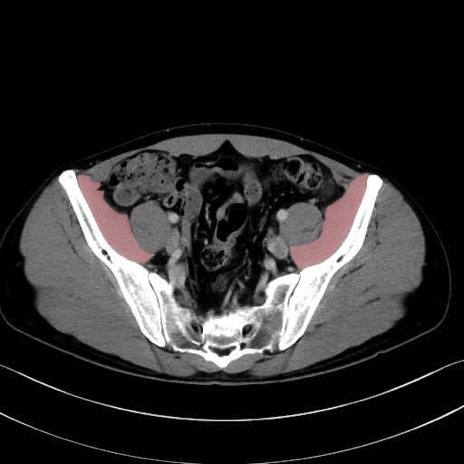

腸骨筋 (Iliacus)